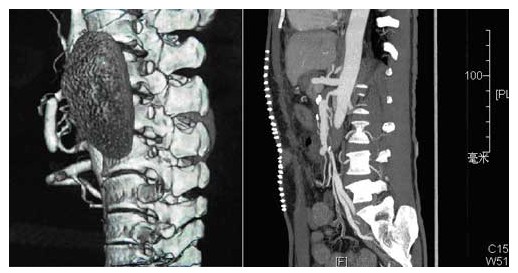

血甲疝科完成一例罕见“孤立性肠系膜上夹层动脉瘤”手术

孤立性肠系膜上夹层动脉瘤手术前、后影像对比图